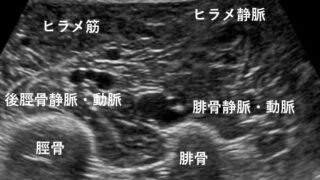

【DVTを見逃さない】下肢静脈エコー上達のコツ|描出安定・圧迫法・2-point法の考え方

下肢静脈エコーが難しいと感じていませんか?本記事では、圧迫法の基本、下腿3分枝の同定、DVTの好発部位、2-point法の考え方までを整理。初学者〜習得途中の技師さんに向けた実践的な上達のコツを解説します。